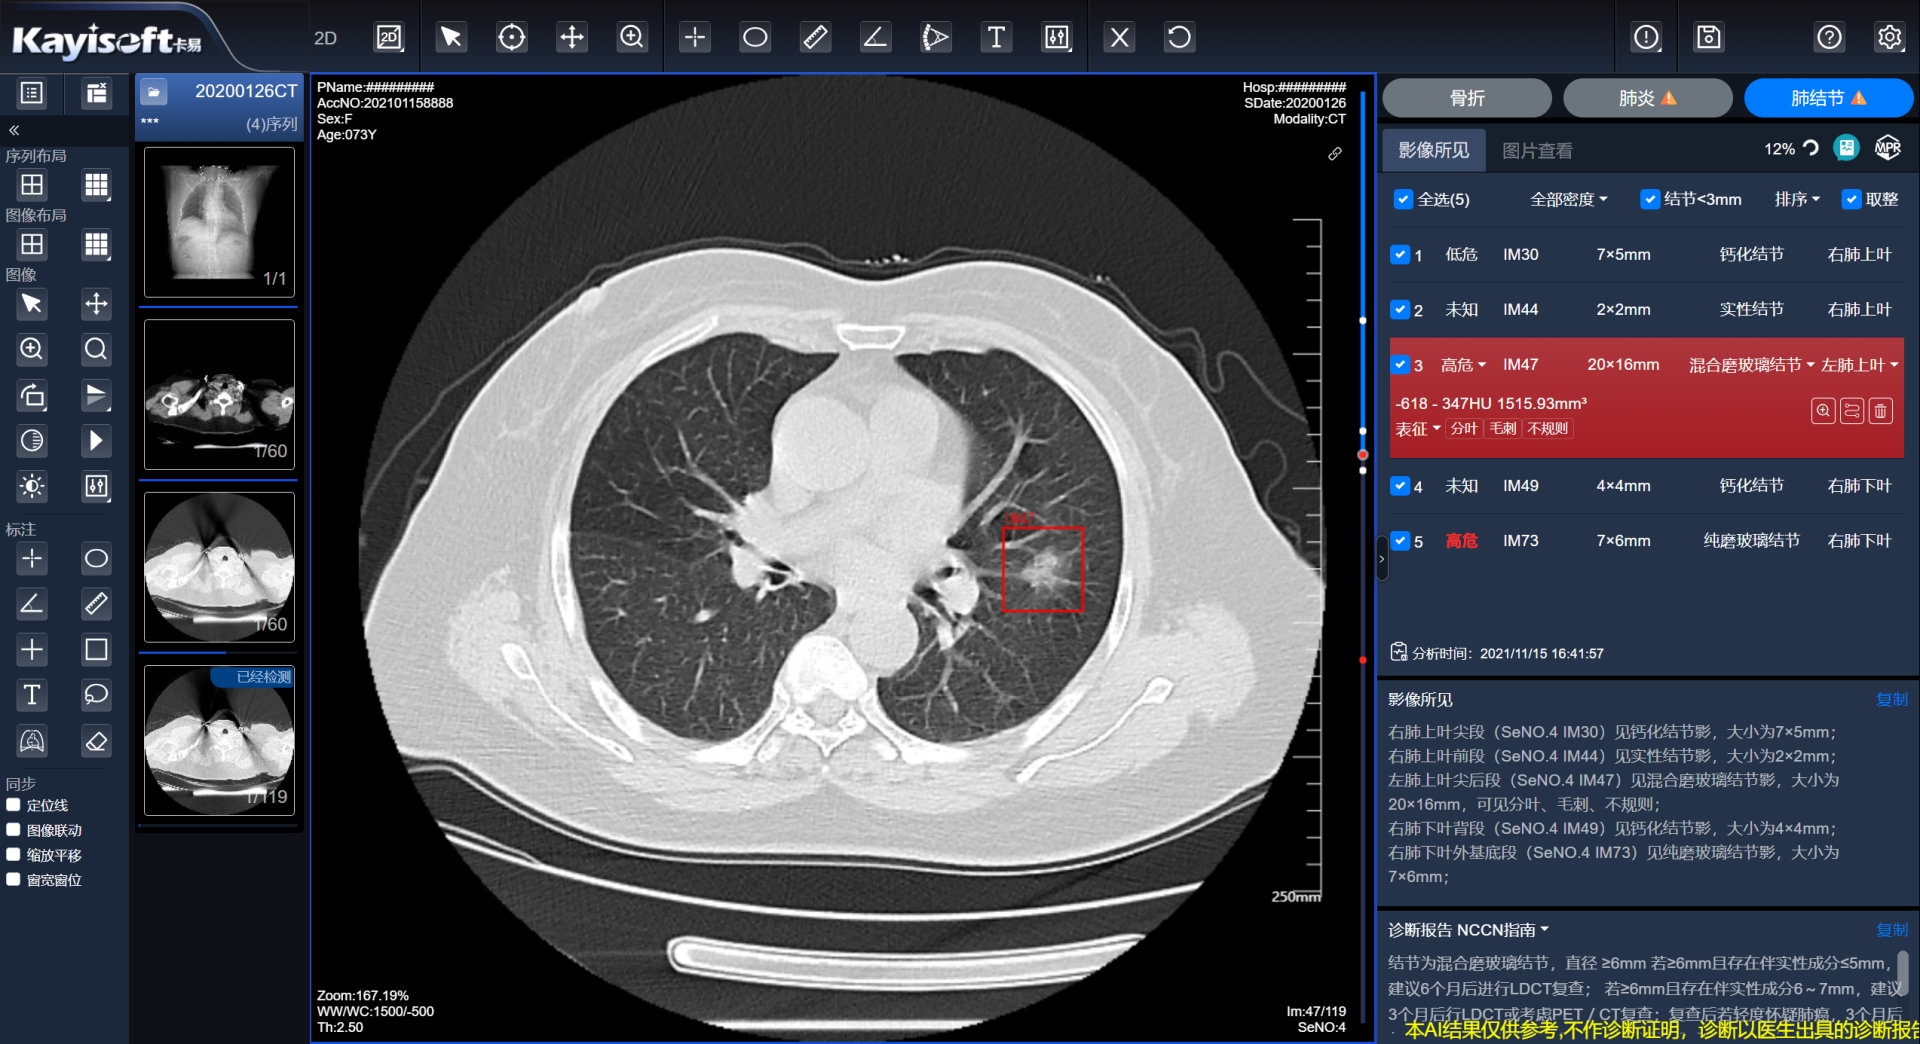

»ùÓÚÇøÓòÓ°ÏñÔÆµÄCT·Î½á½ÚAIÆÊÎöЧÀÍ

ͨ¹ýÈ«ÊÐҽѧӰÏñÔÆÆ½Ì¨Íê³ÉÇøÓòÒ½ÁÆÓ°ÏñÊý¾ÝÔÆ»¯ÖÎÀíÊý¾ÝͳһÊÕÂÞ£¬£¬£¬£¬ £¬ÊµÏÖÒÔÊý¾ÝΪ»ù´¡£¡£¡£ ¡£¡£¡£¬£¬£¬£¬ £¬ÍŽá AI ÆÊÎöЧÀͷνá½ÚÖÇÄܱê×¢£¬£¬£¬£¬ £¬ÔÚ¶Ìʱ¼äÄÚÆÊÎöÍê³É²¢ÌìÉú¡°AI½á¹¹»¯±¨¸æ¡±ºÍ¡°Ö¸Äϲο¼¡±À´Ð­ÖúÕï¶ÏÒ½Éú²Î¿¼£¬£¬£¬£¬ £¬Ìá¸ßÊÂÇéЧÂÊ¡£¡£¡£ ¡£¡£¡£

AIÆÊÎöЧÀÍ+È˵ÄÓÅÊÆ×éºÏ£¬£¬£¬£¬ £¬ÆäÓ°Ïì²»µ«½öÔÚÓÚïÔÌ­ÖØ¸´ÀͶ¯£¬£¬£¬£¬ £¬ÌáÉýÊÂÇéЧÂÊ£¬£¬£¬£¬ £¬ïÔÌ­ÒòÆ£Àͱ¬·¢µÄ©ÕïÕ÷Ï󣬣¬£¬£¬ £¬¸ü´óµÄ×÷ÓÃÔÚÓÚ×ÊÖúÒ½ÉúÖ°ÄÜÈöɣ¬£¬£¬£¬ £¬ºÏÀíÓÅ»¯ÈËÁ¦×ÊÔ´ÉèÖ㬣¬£¬£¬ £¬ÈÃÒ½ÉúÌù½ü»¼Õߣ¬£¬£¬£¬ £¬Ô½·¢×¨×¢ÓÚÓëÁÙ´²ÖÎÁÆÏàÍŽáµÄÖÇ»ÛÀͶ¯¡£¡£¡£ ¡£¡£¡£

AIÆÊÎöЧÀÍ+Ó°ÏñÔÆµÄÓÅÊÆ×éºÏ£¬£¬£¬£¬ £¬Äܹ»Í³³ïЧÀÍÆ÷×ÊÔ´£¬£¬£¬£¬ £¬Í³Ò»Î¬»¤±ãÓÚÖÎÀí£»£»£»£»£»£» £»×ÊÔ´·ÖÅÉÔ½·¢Ôȳƣ¬£¬£¬£¬ £¬Ê¹µÃϲãÒ½ÔºÒ²Äܾ߱¸´óÐÍÈý¼×Ò½ÔºµÄÕï¶ÏÄÜÁ¦£»£»£»£»£»£» £»¸÷Ò½Ôº¿Éͨ¹ý»ùÓÚÓ°ÏñÔÆ·Î½á½ÚAIÆÊÎöЧÀÍʵʱµ÷ÔÄÓ°Ïñ£¬£¬£¬£¬ £¬Õë¶ÔÈ«ÊйæÄ£Äڵķνá½Ú²¡Àý¾ÙÐÐÁ¿»¯Ö¸±êµÄͳ¼ÆÆÊÎö¡£¡£¡£ ¡£¡£¡£